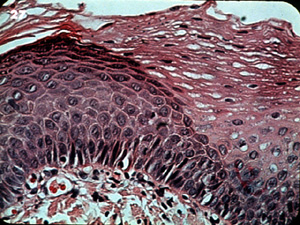

La diferencia entre la queratinización

y el epitelio no queratinizado se ilustra bien aquí. Los núcleos de

las células queratinizadas son más grandes y más prominentes; esto

proporciona la apariencia más oscura del tejido. Las células, sin

embargo, son bastante uniformes y no hay atipías. |